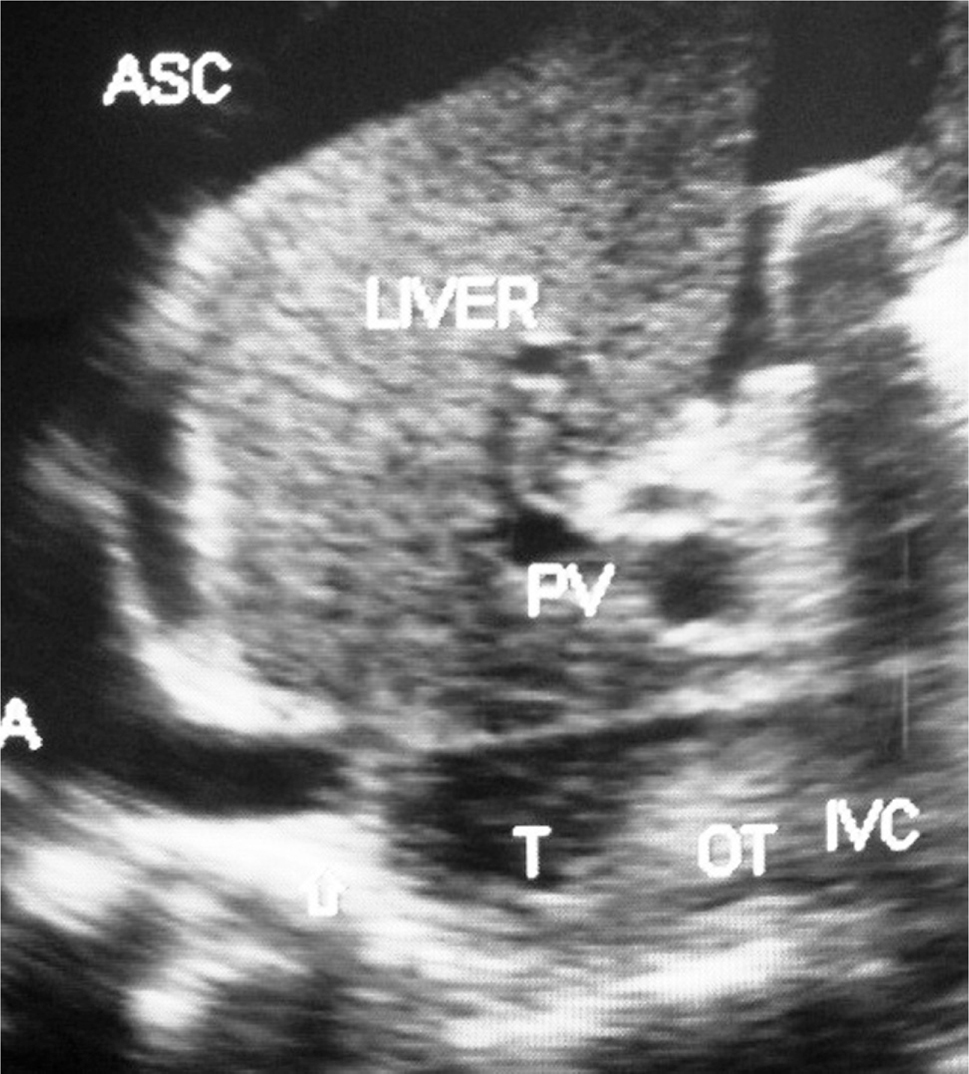

Fig 3

Figure 3. Hepatic vena cava syndrome: Ultrasonography of a young patient with ascites showing localized stenosis of upper segment of IVC with distal dilated segment of the IVC filled with recent and old organized thrombi. ASC, ascites; IVC, inferior vena cava; OT, organized thrombus; RA, right atrium; T, thrombus. (Copyright: Santosh Man Shrestha).